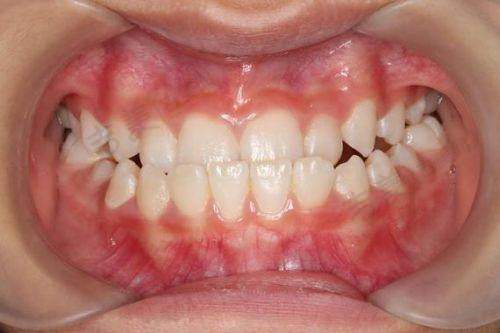

宋小培医生——双学科带头人:宋小培是上海科特满口腔·全科&正畸中 心坐诊医生,毕业于厦门医学校口腔医学系,现任中华口腔医学会会员、上海科特满口腔全科与正畸双学科带头人。在牙体牙髓领域,熟练掌握显微根管、热牙胶三维充填、MTA生物修补等潮流技术,前牙美学树脂分层修复病例累计超过8000例,后牙微创嵌体保存率高;在正畸方向,系统研修MBT直丝弓、隐形矫治(隐适美/时代天使认证医师)及儿童早期干预矫治,善于利用数字化微笑设计(DSD)与面部黄金比例,为青少年及成人定制个性化矫治方案,隐形矫正完成病例逾500例,平均缩短疗程3 - 6个月,尤为擅长儿童口腔全周期管理。

牙齿矫正项目亮点:牙齿矫正项目涵盖金属托槽6500 - 9800元起,隐适美隐形矫正32800元起。利用3Shape Trios口扫仪即刻呈现矫正后动态结果,可提前“预见”笑容,5分钟生成动态矫正图,患者可预览终咬合,方便患者选择适合自己的矫正方案。

宋小培医生的出色表现:宋小培医生作为全科与正畸双学科带头人,在牙体牙髓和正畸领域都有出色的表现。在牙体牙髓方面,熟练掌握多种精良技术,积累了大量成功病例;在正畸方面,能为不同年龄段的患者定制个性化矫治方案,缩短矫正疗程。